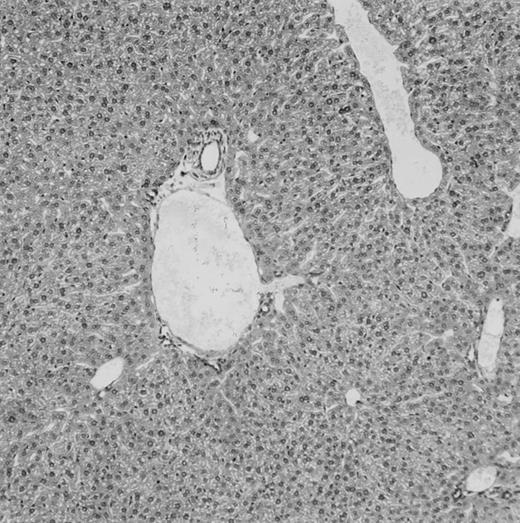

Histologic findings. Organs were collected at different times after BMT and tissue sections were stained with hematoxylin and eosin. Original magnifications for spleen (left) and liver (right) are ×40 and ×100, respectively. (A) B6 mice receiving FVB BM plus EpTK T cells. (B) Control group receiving BM only.

FVB BM-grafted B6 mice: a model of lethal GVHD.We developed a model of GVHD resulting in 100% mortality soon after BMT using FVB mice, a strain not previously used as BM donors in experimental allogeneic BMT. We tested different combinations of recipient irradiation doses, as well as injected BM cell and CD3+ peripheral T-cell numbers. When 10-Gy–irradiated B6 mice were reconstituted with 107 FVB BM cells, we observed prolonged survival, whereas all ungrafted animals died before day 16 (Fig 2). In these conditions, more than 98% of splenocytes were of donor origin (Fig 3A). When 107 CD3+ peripheral T cells from mice of FVB genetic background were added to the FVB BMT, all animals died of GVHD between days 7 and 34 (Fig 2). Similar results were obtained using either PBS-treated mice receiving EpTK or EpΔTK peripheral T cells or GCV-treated mice receiving FVB nontransgenic peripheral T cells. Notably, this observation also indicates that both TK- and ΔTK-expressing T cells in the absence of GCV are fully competent to induce a lethal GVHD. Histopathologic examination of spleen and liver of these animals showed characteristic GVHD lesions such as (1) architecture disruption, necrosis, and congestion in the spleen; (2) hepatic periportal necrosis; (3) mononuclear portal infiltrates; and (4) endothelialitis of portal or centrolobular veinules (Fig 4A). By comparison, B6 mice receiving only FVB BM had a normal histology (Fig 4B).